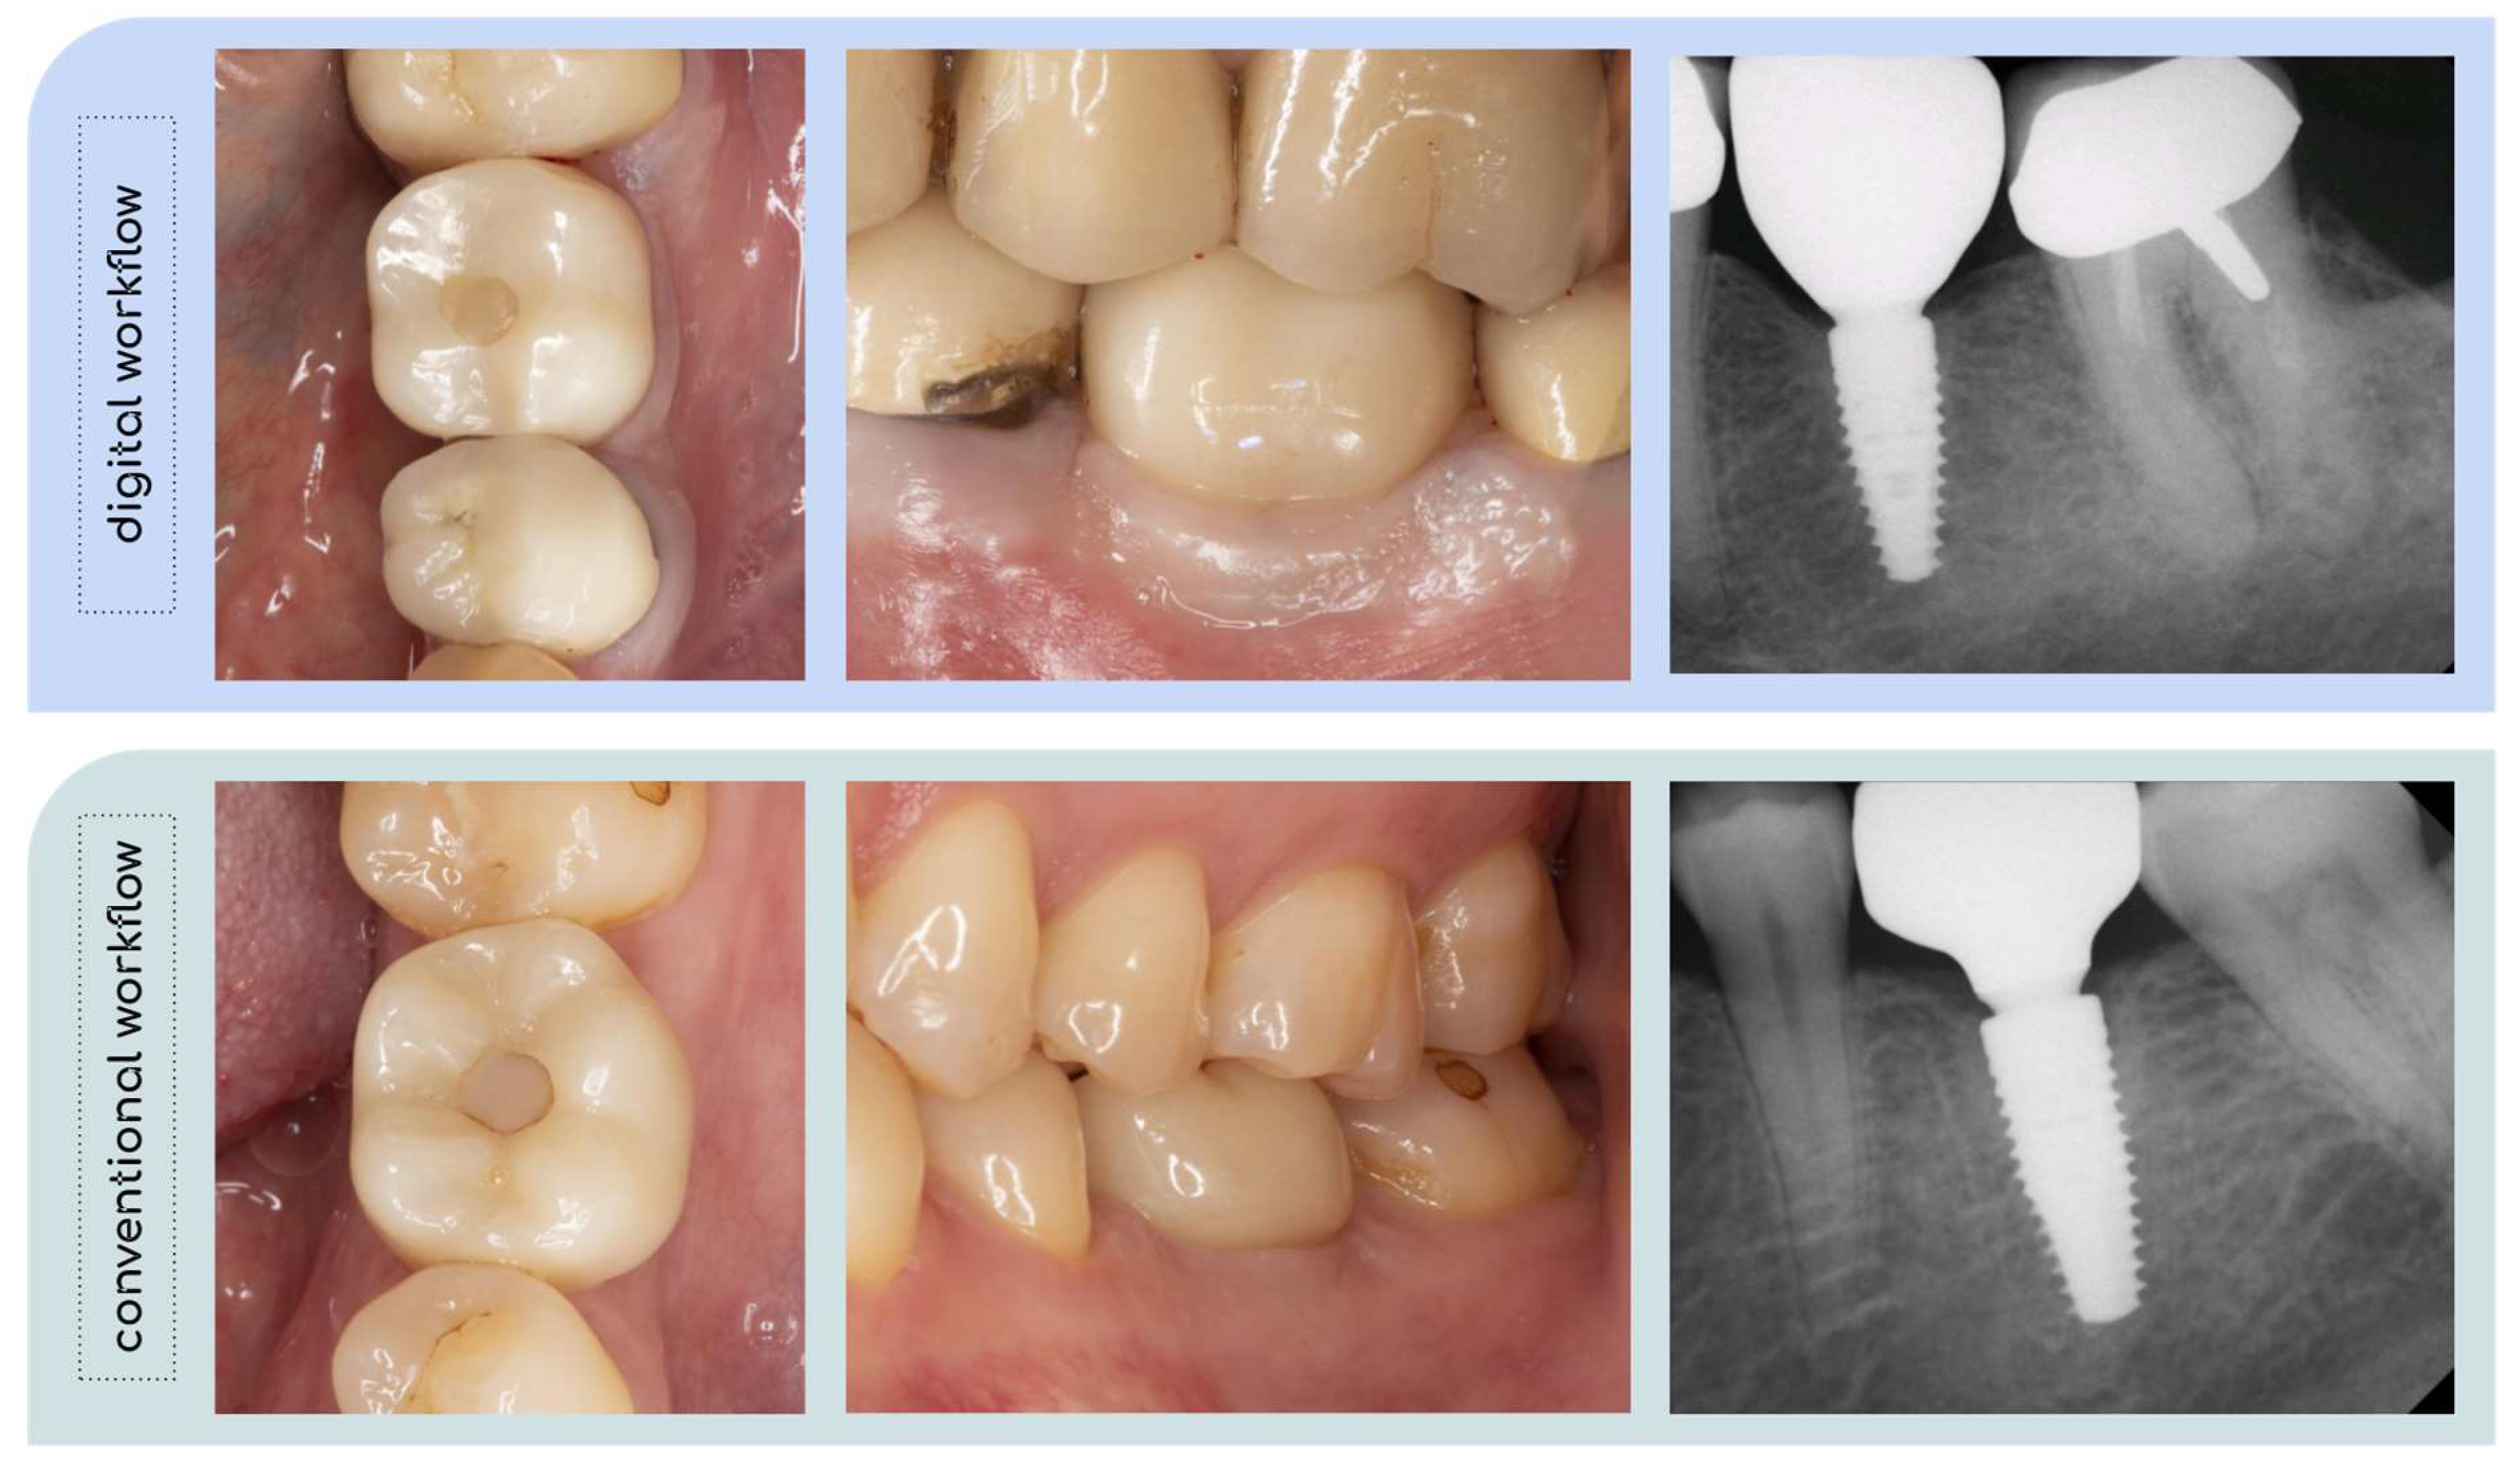

Clinical and Radiographic Outcomes of Single Implant-Supported Zirconia Crowns Following a Digital and Conventional Workflow: Four-Year Follow-Up of a Randomized Controlled Clinical Trial

2.3. Digital Workflow (Test Group)

2.4. Conventional Workflow (Control Group)